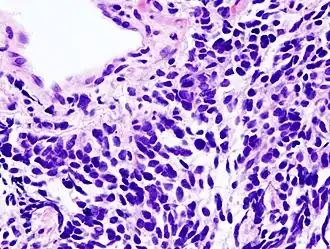

Carcinoma de células pequeñas.

Carcinoma de células pequeñas (SCLC)

Vista microscópica de una biopsia de carcinoma de pulmón de células pequeñas.

Cerca de un 15 % de todos los carcinomas de pulmón se corresponden con un cáncer de pulmón de células pequeñas, también llamado carcinoma de células de avena.[48]​ Tiende a aparecer en las vías aéreas de mayor calibre —como en los bronquios primarios y secundarios— y crece rápidamente llegando a tener un gran tamaño.[49]​ La célula de avena contiene densos gránulos neurosecretores, es decir, vesículas que contienen hormonas neuroendocrinas, que le da una asociación con un síndrome endocrino o paraneoplásico, es decir, caracterizado por síntomas no relacionados con el efecto del tumor local.[50]​ Aunque es un tipo de cáncer que inicialmente resulta más sensible a la quimioterapia, conlleva un peor pronóstico y se disemina mucho más rápidamente que el cáncer pulmonar de células no pequeñas.[48]​ Los tumores de pulmón de células pequeñas se dividen en una etapa limitada y una etapa avanzada o diseminada. Este tipo de cáncer está igualmente asociado al tabaquismo.[51]​ Este tumor se asocia más que los anteriores a síndromes paraneoplásicos por secreción ectópica de hormonas.[52]